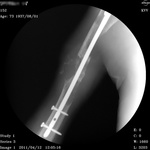

Пол пациента: Мужской пол Тип патологии: Злокачественное новообразование Область исследования: Скелетно-мышечная система Методы исследования: Rg ID:13335 Втр, 12/04/2011 - 07:24 #1 Vikkur Не на сайте Был на сайте: 4 года 8 месяцев назад Зарегистрирован: 24.09.2009 - 14:34 Публикации: 1749 Rv ...Приложения: Виктор. Втр, 12/04/2011 - 21:11 #2 tatyana Не на сайте Был на сайте: 4 года 1 месяц назад Зарегистрирован: 24.06.2009 - 08:33 Публикации: 2090 мтс множественные, возможно - имплантационные, резекция - сомнительна, вероятнее - биопсия "самоуверенность дилетантов - предмет зависти профессионалов" Чт, 14/04/2011 - 03:30 #3 Vikkur Не на сайте Был на сайте: 4 года 8 месяцев назад Зарегистрирован: 24.09.2009 - 14:34 Публикации: 1749 Вы полностью правы принес сегодня снимки за 2009 - после операции.Приложения: Виктор.

Вы полностью правы принес сегодня снимки за 2009 - после операции.